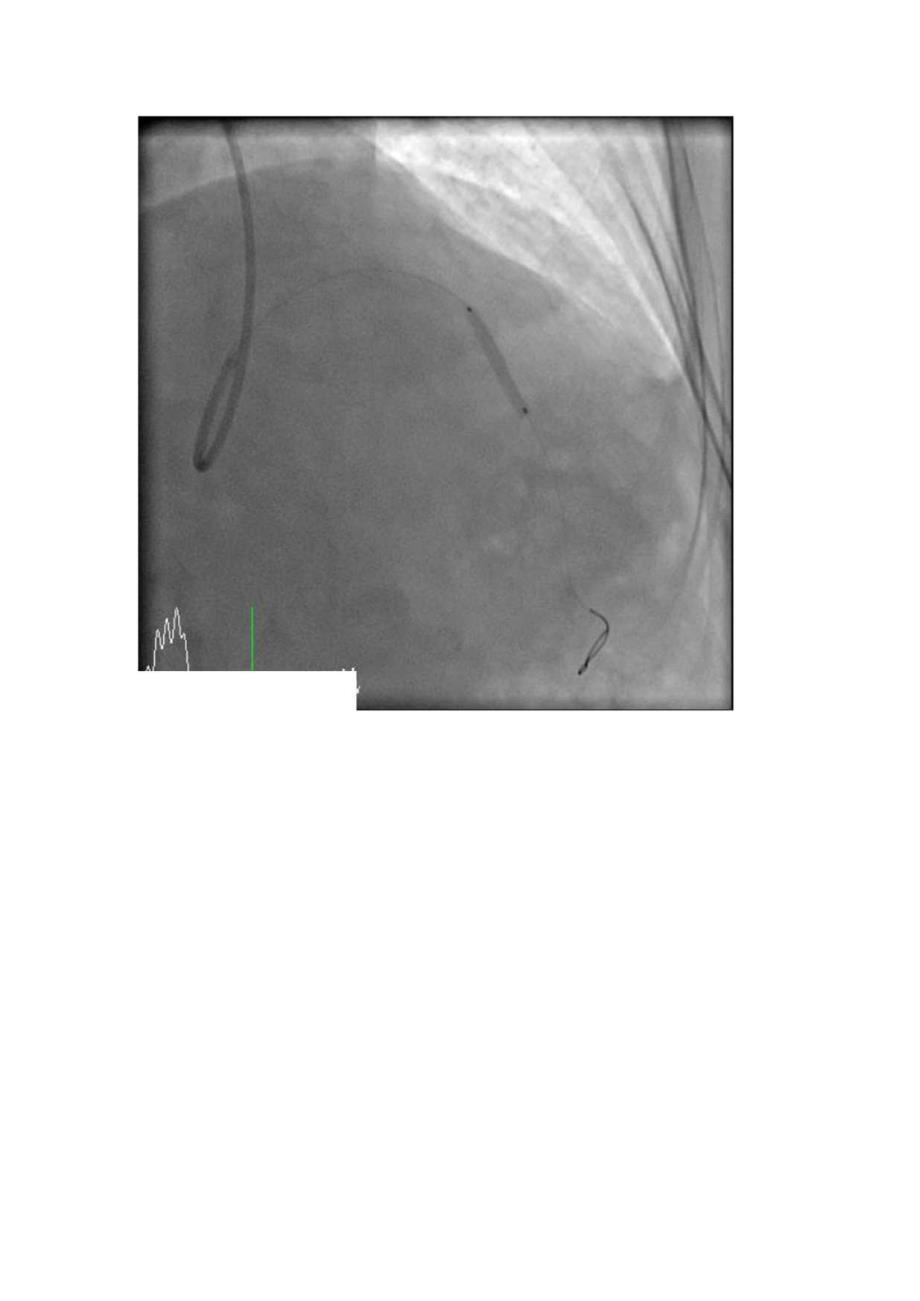

2、5V6导联ST段近似水平型压低0.5mm,20190623于我院查冠状动脉CT示:左冠前降支中段心肌桥,伴管腔重度狭窄。48小时主治医师诊断:冠心病不稳定心绞痛;高血压3级,很高危;脑梗个人史签名初步诊断:冠心病不稳定心绞痛;高血压3级,很高危;脑梗个人史初步诊断:冠心病不稳定心绞痛;高血压3级,很高危:脑梗个人史动脉造影结果初析:LM:未见明显狭窄,LAD:近中段85%狭窄,狭窄后心肌桥,LCX:优势,未见明显狭窄,RCA:中段管壁不规则。左心室造影:收缩功能可。主动脉根部造影:未见明显异常。介入治疗:对LAD病变血管行PCI。经鞘管插入6F导引导管,经导管送入Sion导丝,2.5*15mm球囊8atm预扩;3.0*2Omm药物球囊8atm扩张30s释放,再造影见残余10%狭窄。退出导管导丝,拔除动脉鞘管,无菌纱布覆盖,安返病房。术后处理详见医嘱。术中血动力学检测:血压:140/7OmmHg,心率:75次/分,主动脉压力:14065mmHg,血氧饱和度:100%。术中情况:患者无胸痛,无手术并发症。术后注意事项:注意患者胸闷胸痛症状,注意术后心电图、心梗三合一等变化,嘱患者静心休息。